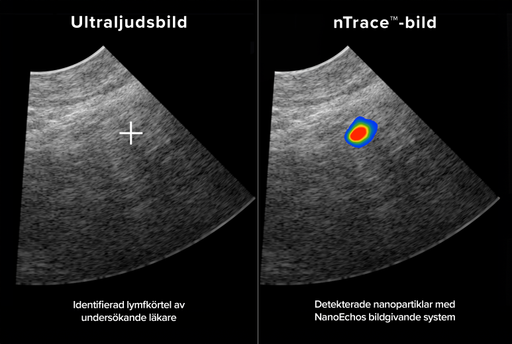

NanoEcho AB (publ) presenterar idag för första gången en bild från en klinisk undersökning. Bilden visar hur vibrerande järnoxidbaserade nanopartiklar – den så kallade nTrace-signalen – detekteras i en lymfkörtel hos en människa med bolagets diagnostiska system.

Den bifogade bilden togs inom ramen för den nyligen avslutade dosbekräftelsestudien på en av studiedeltagarna. Bilden är en av flera liknande bilder som låg till grund för de resultat som kommunicerades den 2 april 2025. Då meddelade NanoEcho att de primära målen i dosbekräftelsestudien uppnåtts – att både lämplig dos av nanopartiklar och ett lämpligt tidsintervall för efterföljande undersökning med NanoEchos diagnostiska system fastställts hos friska studiedeltagare. Redan som ett resultat av en tidigare interimanalys, publicerad den 20 december 2024, kommunicerades att järnoxidbaserade nanopartiklar identifierats i lymfkörtlar hos friska studiedeltagare. Detta visas nu i den publicerade bilden.